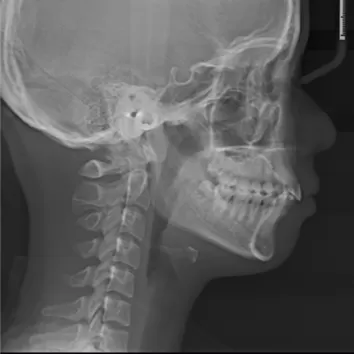

Rayons X avant le traitement

[Radiographie panoramique/Céphalogramme latéral]